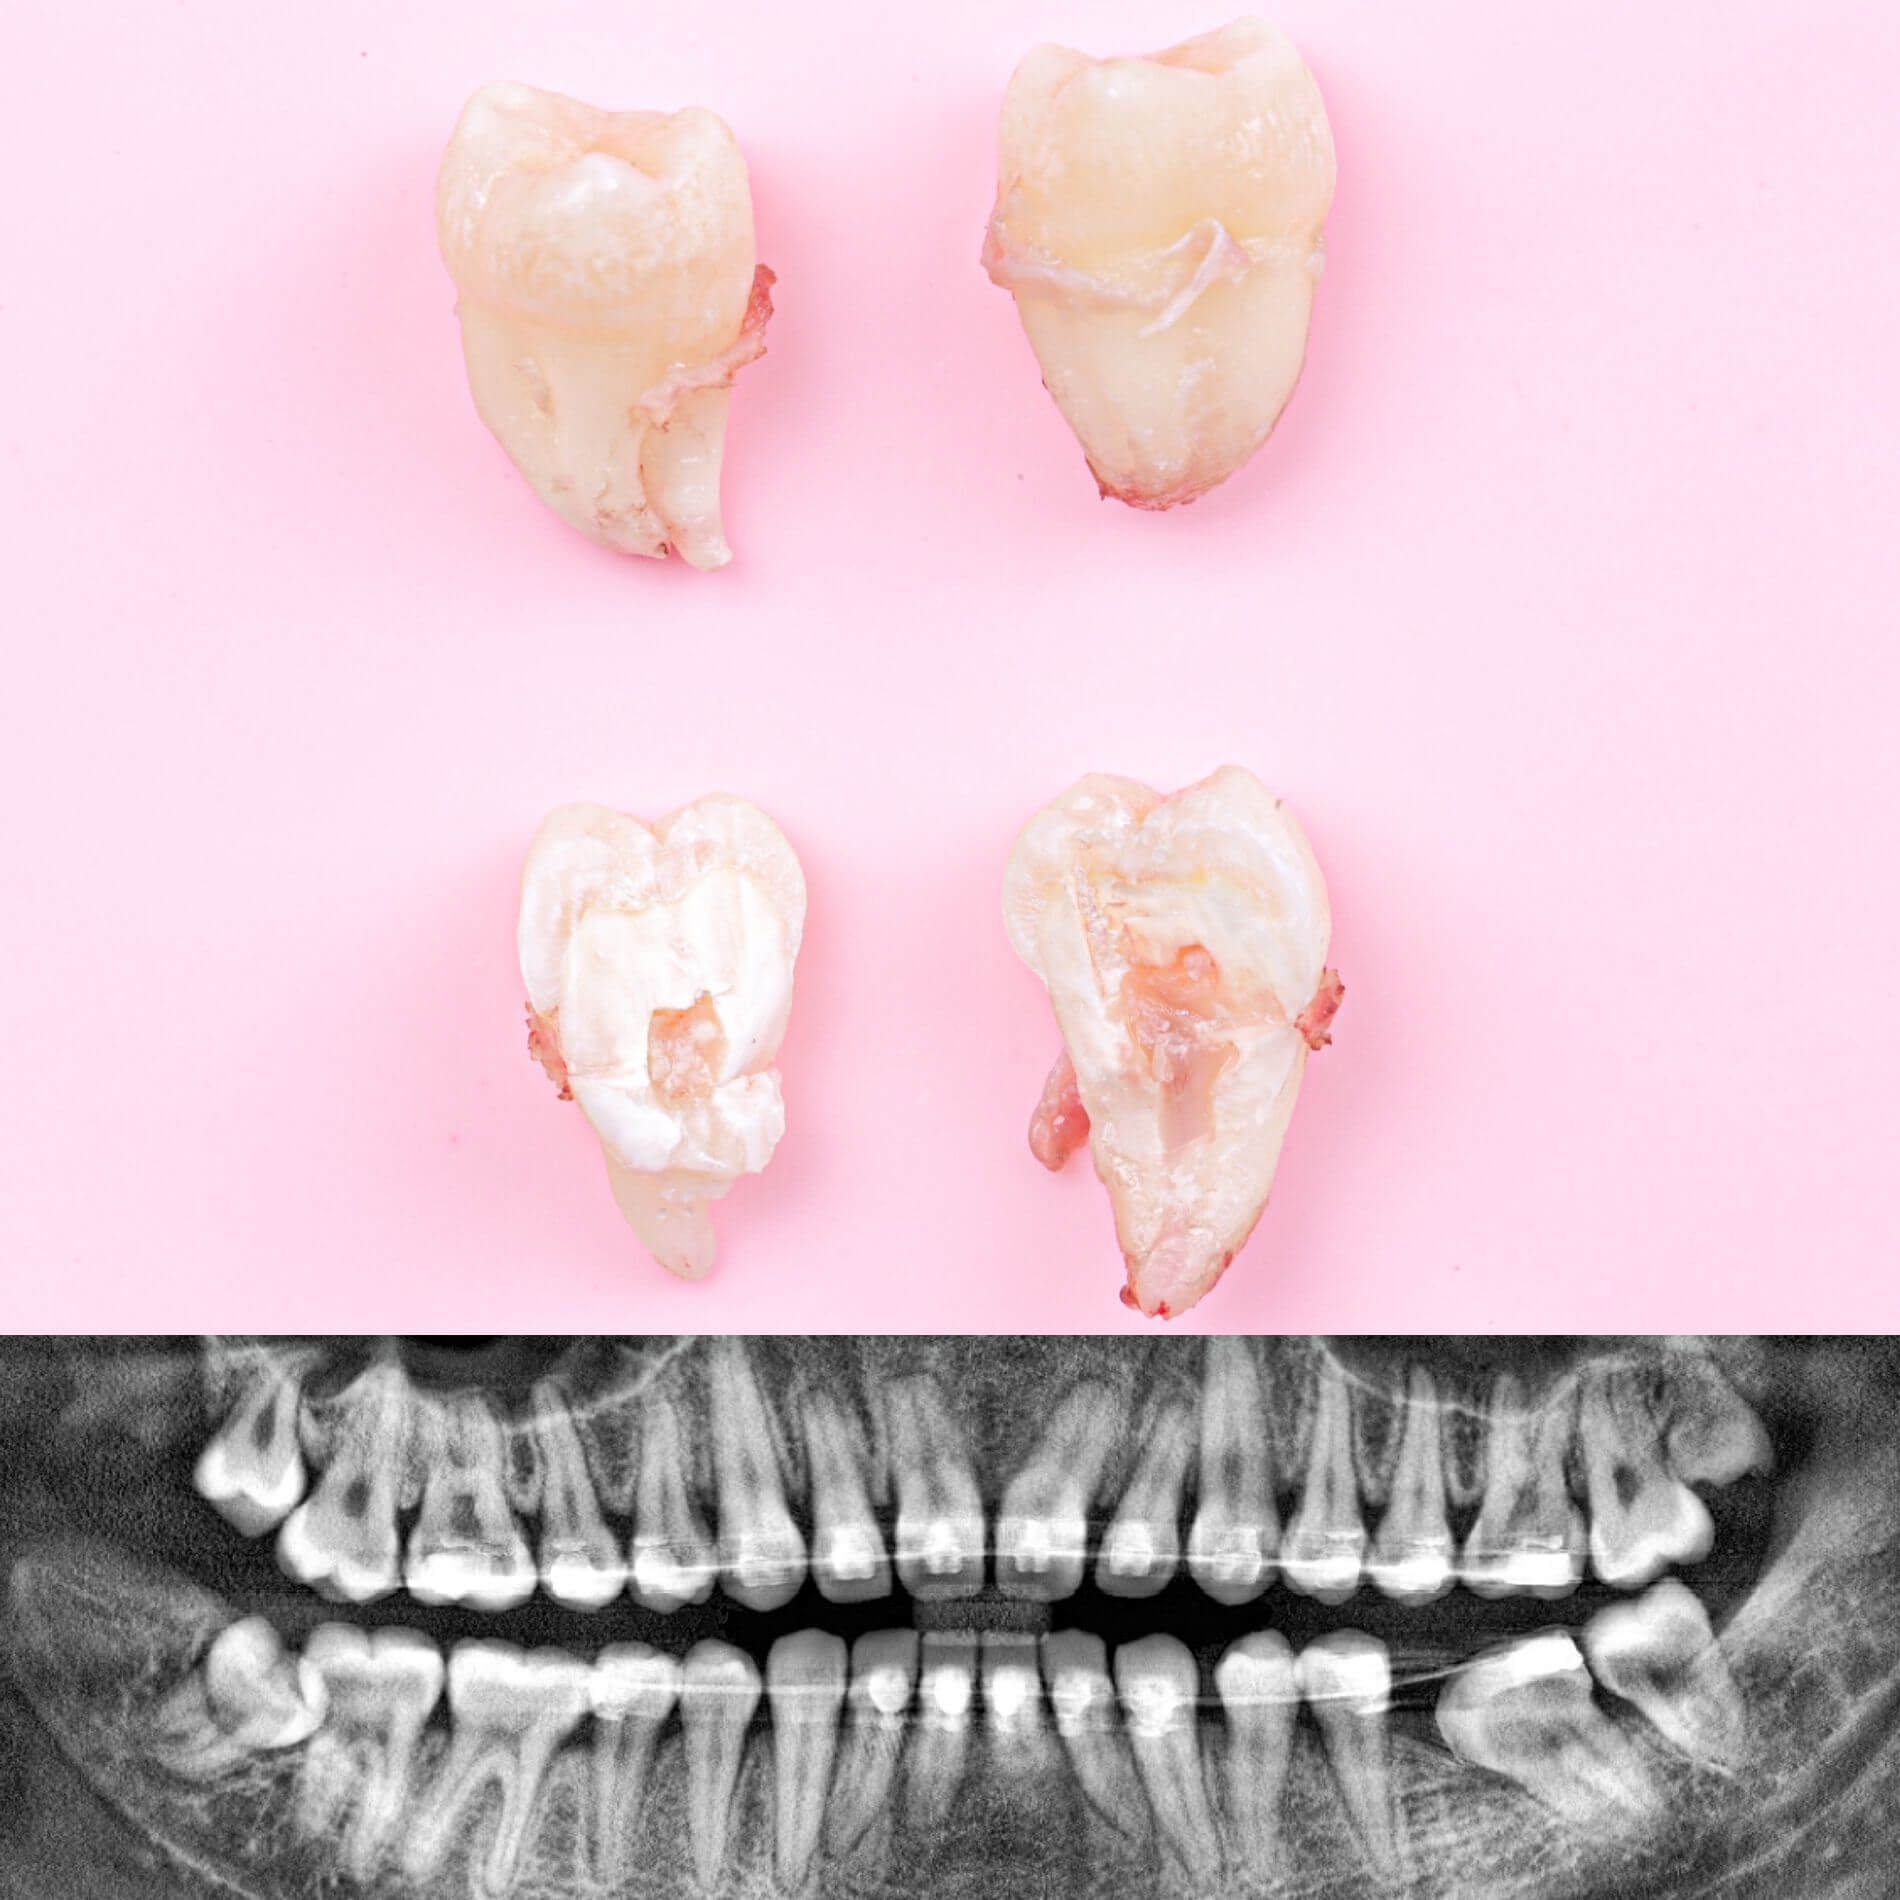

• Полное удаление зуба - если зуб полностью прорезался и имеет сросшиеся корни.

• Отдельное удаление коронки зуба и его корней - если зуб прорезан и корни растут по отдельности.

• Удаление зуба по схеме 1 или 2 с разрезом десен - если зуб прорезан частично.

Галерея